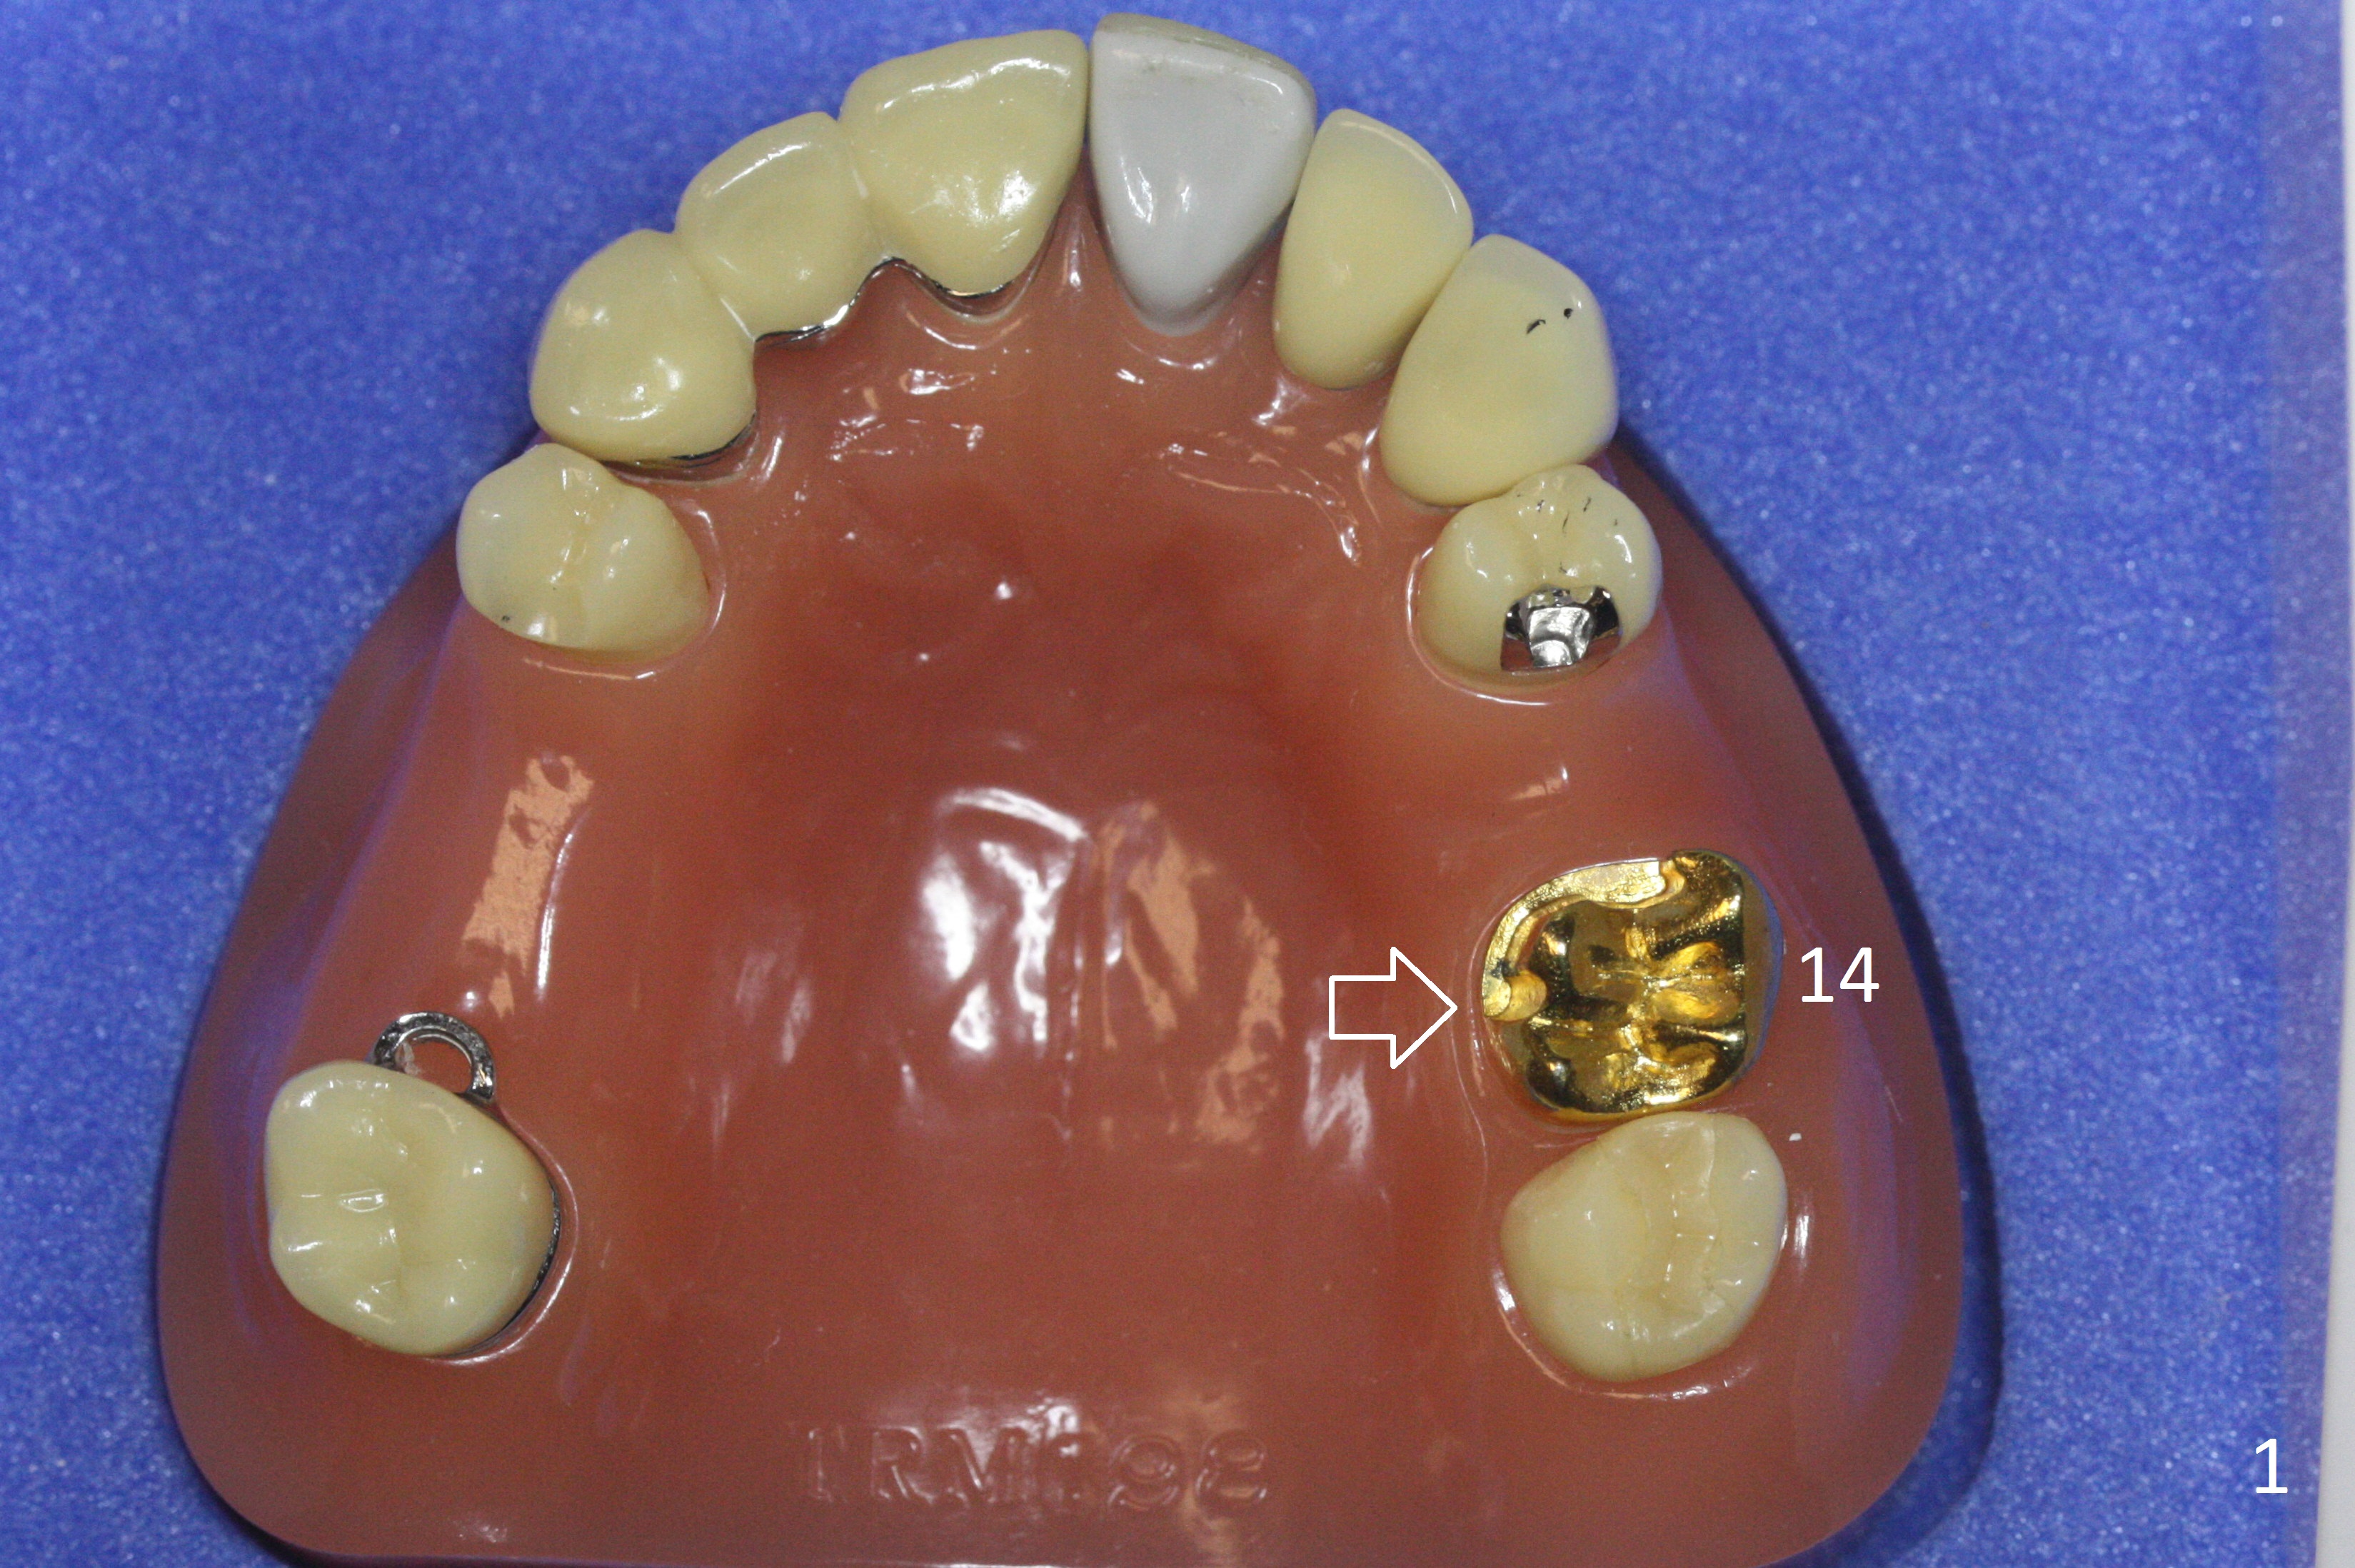

Also simplify design.  For example, in a demonstration model, there is mesiopalatal prep in the crown at #14 (Fig.1 arrow).  The lingual clasp is short, stopping the distal end of the prep (Fig.2 arrow).  There is no buccal clasp.